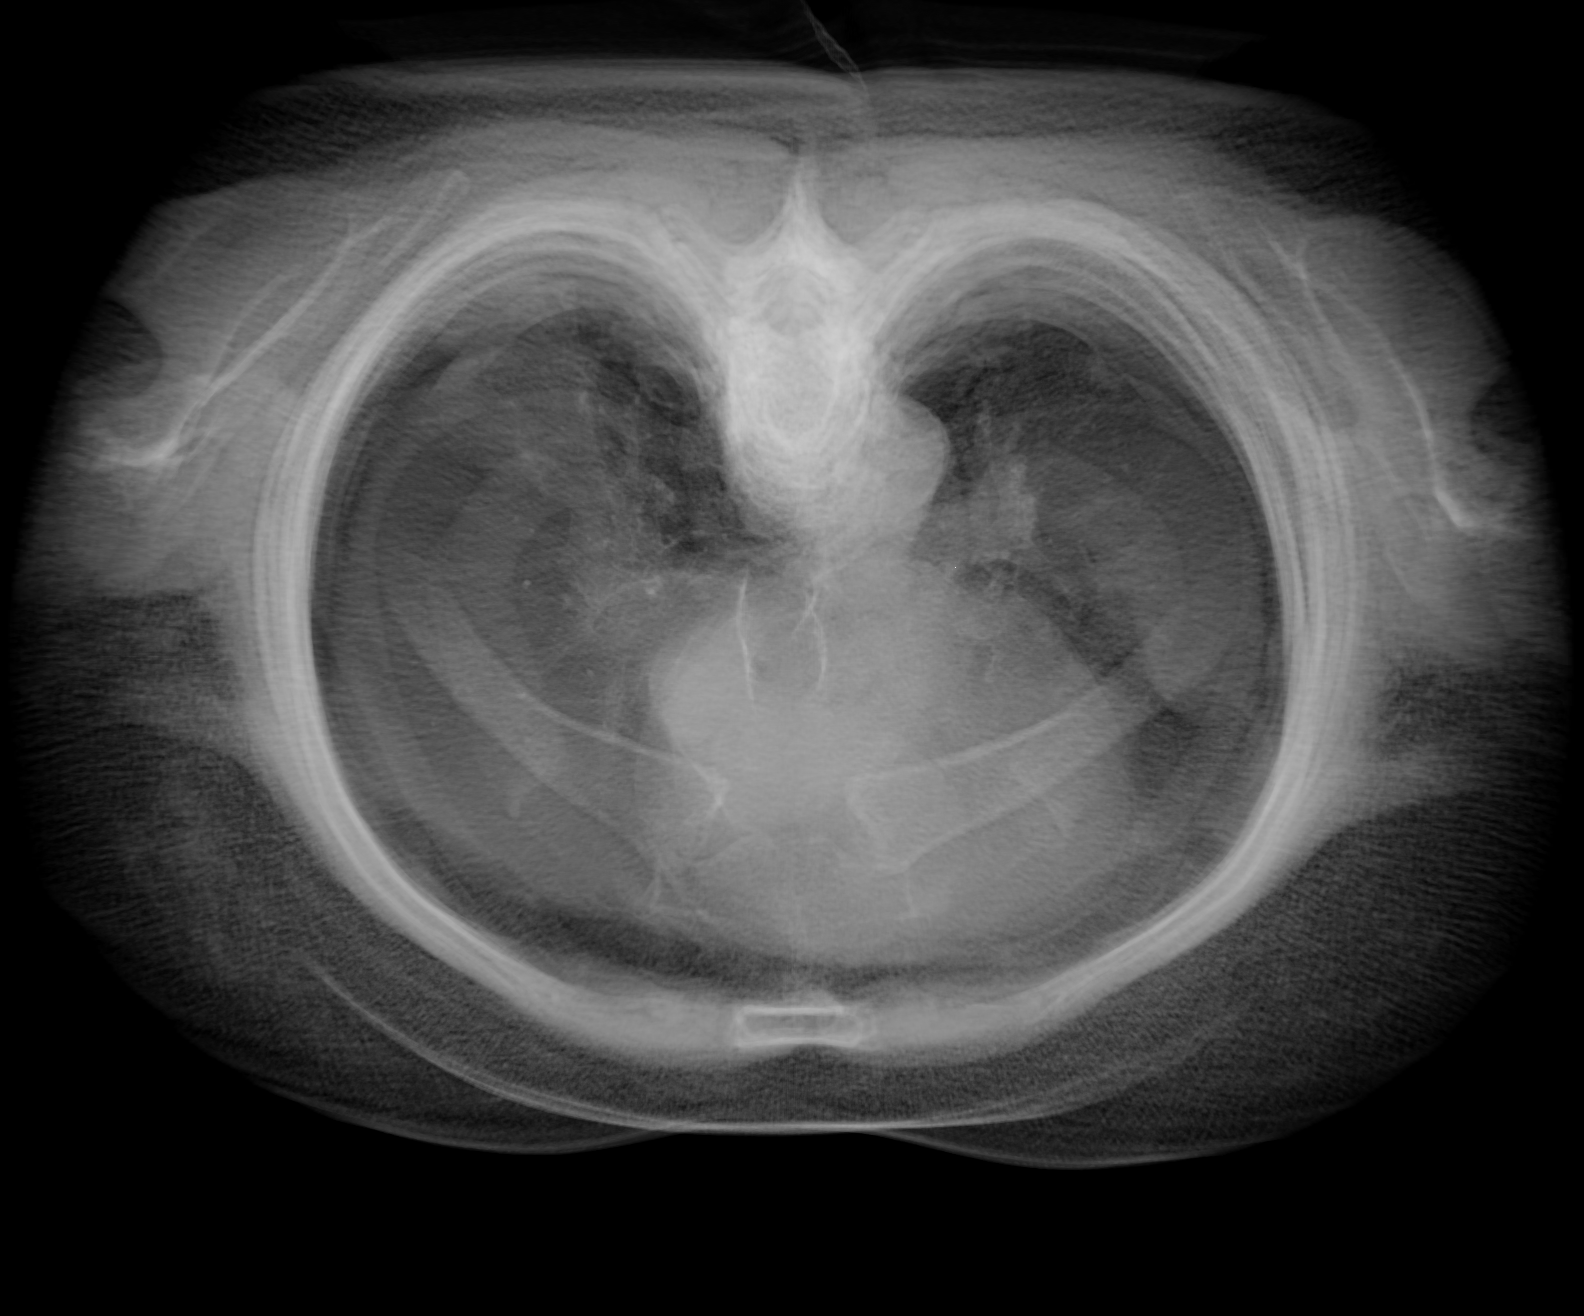

step2-8bit.png (1.2 MB ) - added by Tom Goddard 7 years ago.

Step 2, 8-bit rendering.

I attached 6 example images of a lung CT scan (folder 4-24533), grid size 512 x 512 x 236, 3d projection rendered with plane spacing minimum along 3 axes, voxel size .576 x .576 x 1.25, so about 500 planes, view along z axis, perspective projection. Step 1 and 2 look quite different with normal 8-bit rendering, but look nearly the same with 16-bit rendering. Both 16-bit framebuffer and 16-bit color/alpha texture contribute have significant effect on the appearance.